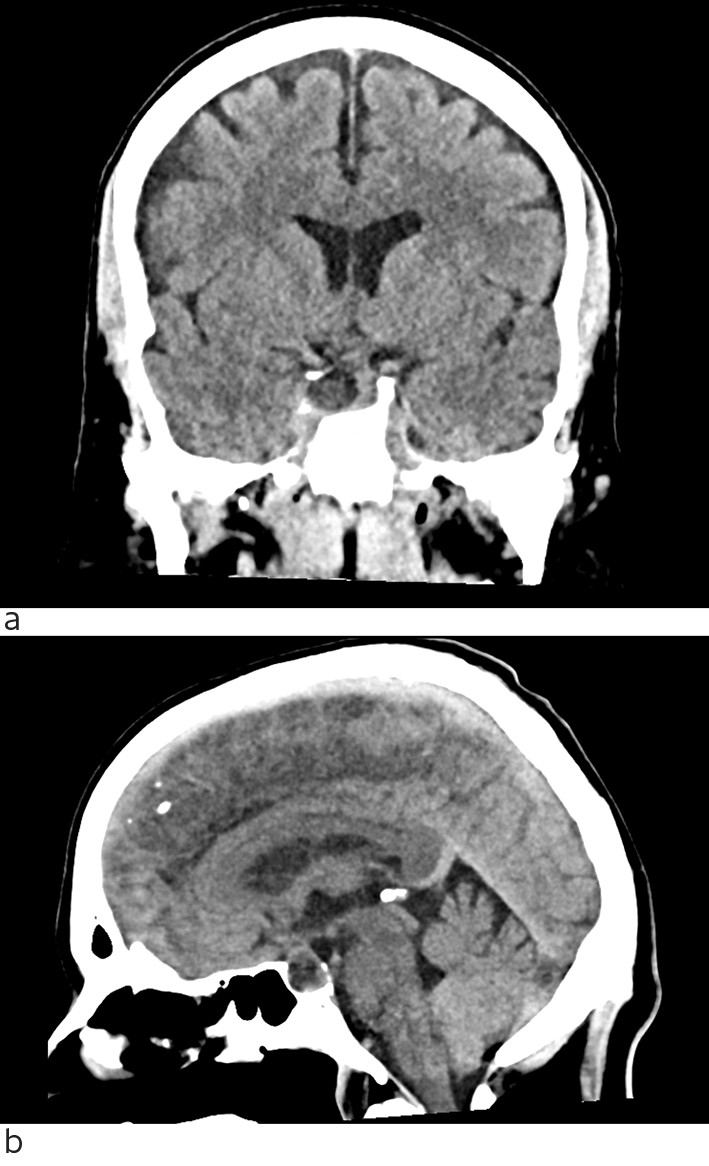

Ved regranskning så man at CT caput tatt ved innleggelsen viste en lavattenuerende lesjon i hypofysen (fig 2). MR caput tatt som øyeblikkelig hjelp-undersøkelse viste blødning i et hypofyseadenom med bukning inn i sinus cavernosus på høyre side og affeksjon av nervus abducens. Det var ekspansjon av sella turcica med manglende laterale høyre vegg og kraftig uttynning av bakre vegg, som var forenlig med et adenom som hadde utviklet seg over lang tid med remodellering av omliggende ben. Det var også noen uspesifikke lesjoner i hvit substans. Pasienten ble samme kveld overført til nevrokirurgisk avdeling ved universitetssykehus. Han ble operert neste dag med transsfenoidal reseksjon av hypofysetumor og blødning.

En annen lærdom fra denne sykehistorien er at regranskning av tidligere utførte radiologiske undersøkelser i lys av ny klinisk informasjon kan føre til at man oppdager patologi som har blitt oversett.